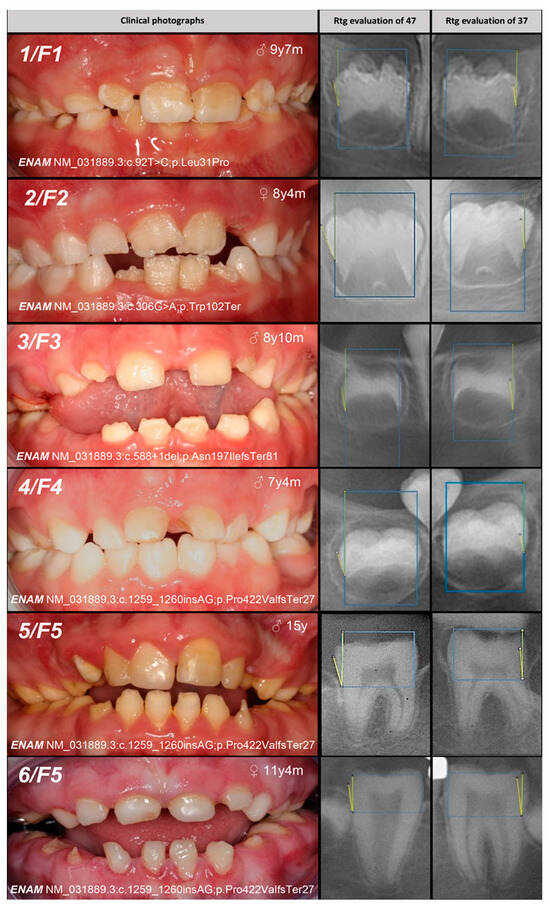

| 1, F1 | Hypoplastic (localized) | IB, AD, ENAM | c.92T>C | +/− | p.Leu31Pro | novel | Mo (AC) Fa (U) | likely pathogenic (PP1:moderate, PM5:moderate, PM2:moderate) |

| 2, F2 | c.306G>A | +/− | p.Trp102Ter | novel | Mo (AC) FaS (U) | likely pathogenic (PVS1:very strong, PM2:moderate) * | ||

| 3, F3 | Hypoplastic (generalized) | c.588+1del | +/− | p.? | [25] | Mo (U) Fa (AC) | pathogenic (PS4:strong, PVS1:strong, PM2:moderate) | |

| 4, F4 | Hypomineralized (hypoplastic) | IB, AD, ENAM | c.1259_1260insAG | +/− | p.Pro422Val fsTer27 | [5] | Mo (AC) FaS (U) | pathogenic (PS4:strong, PVS1:strong, PM2:moderate) GnomAD: 0.0002517 |

| 5, 6, F5 | Hypoplastic (generalized—recessive trait; localized, pitting, grooving—dominant trait) | IC, AR/AD, ENAM | −/− | [25] | MoFa (UC) | |||

| 7, F6 | MoFaS (UC) | |||||||

| 8, F7 | MoFa (UC) | |||||||

| 9, F8 | MoFa (UC) | |||||||